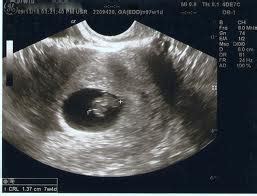

Aku adalah seorang eksekutif muda yang baru diangkat menjadi manajer di sebuah perusahaan swasta di surabaya. Linea nigra adalah sebuah garis hitam atau cokelat pekat yang membentang secara vertikal di atas perut ibu hamil yang biasanya dimulai sejak trimester kedua kehamilan. Garis kehamilan ini disebut dengan linea nigra, yang memiliki. Linea nigra adalah bahasa latin dari garis hitam. Perawatan garis perut linea nigra. Adanya garis perut pada ibu hamil perlu diketahui dan dipastikan dengan benar apakah hal tersebut merupakan kondisi yang termasuk dalam gangguan kehamilan. Garis gelap ini biasanya muncul vertikal di tengah perut anda saat perut anda sudah mulai membesar. Sebenarnya, garis ini mungkin sudah ada di perut anda sebelum hamil.